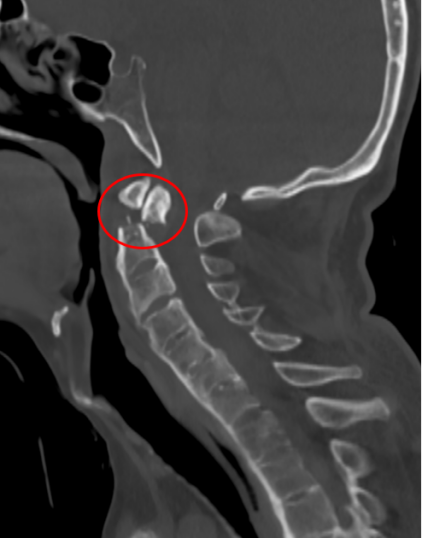

接诊后得知,金先生还患有强直性脊柱炎多年,这种疾病直接的后果是脊柱强直如棍棒,骨质变脆易骨折,被冠名以“不死的癌症”。姜主任详细了解金先生的病史后,认为该患者的治疗关键在于以下三个方面:一是脊柱强直,手术部位的位置深难以显露,解剖复杂。二是C2、C3左侧椎弓根发育异常狭小,置入椎弓根螺钉困难。三是齿状突骨折向后方移位明显,通常向前脱位较为常见复位也较容易,此种脱位的复位具有较大的难度和损伤脊髓的风险,对于术者而言是个巨大考验。

金先生伤后第7天,姜主任医师团队在麻醉手术科的密切配合下成功为他实施手术。姜主任凭借多年徒手置钉的过硬技术经验,2小时不到便完成了手术,术中出血仅100ml。术后CT显示齿状突完美复位,螺钉“不偏不倚”的位置恰到好处。术后,金先生在骨科护士长张霞芬护理团队的精心护理下,15天后伤口拆线康复出院。

第一步是先从颈椎后方入路,使用手术器械将骨折脱位复位,然后用螺钉固定;第二步是待患者恢复一段时间后再行前路手术。这个术式的难点在于强直性脊柱炎患者有严重的骨质增生表现,解剖标志不清,置钉有难度;其次,CT显示后方关节突交锁,复位困难。姜主任再次凭借多年手术经验,在二代0臂机的保驾护航下,成功地将螺钉置入椎体内,手术历经3小时。术后,金先生的右侧肢体偏瘫有了明显改善,2周后出院。